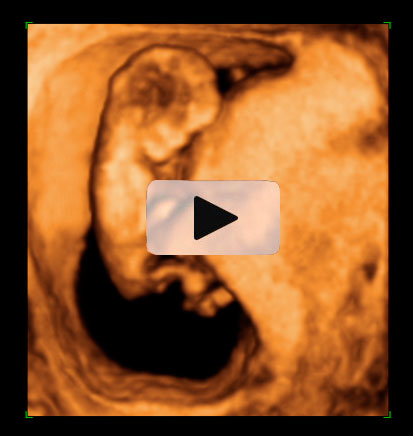

Ecografía 4D de la semana 12: Feto mirando "a la cámara"

Esta ecografía 4D muestra a un bebé de 12 semanas de gestación que se encuentra situado contra la pared del útero materno. El feto parece mirar varias veces hacia el ecógrafo y se tapa la cara con los brazos. Puede observarse con gran detalle la estructura ósea de la mano.

Ecografía en 4D de un feto de 12 semanas "mirando a la cámara"

A este niño de 12 semanas de gestación parece que le ha "pillado" el ecógrafo desprevenido y se quiere esconder. El bebé está contra la pared uterina: se da cuenta de que el ecografista le está "enfocando" y parece con si se quisiera esconder del público, como las estrellas de cine. Mira varias varias veces "a cámara", en una actitud sorprendente; se tapa la cara con los brazos. La mano se perfila perfectamente, así como muchas de sus estructuras óseas, mientras se esconde cara a la pared uterina.